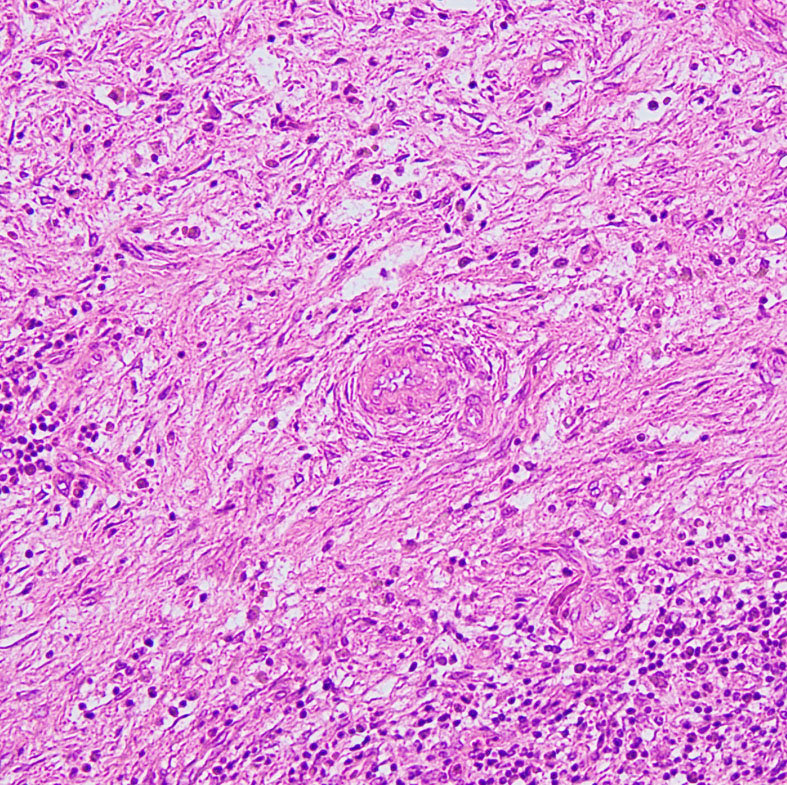

LCHの病理像

頭蓋骨のLCHの病理像です。左はHE染色,右はランゲルハンス細胞に特異性の高いCD1a(specific to dendric Langerhans cells) 染色です。多数のLangerhans cellとともに,組織球,リンパ球,好酸球,多核細胞など多彩な細胞浸潤があります。これは活動性のLCHの病巣から摘出したものです。

自然緩解して収まった病巣を生検術で摘出しても,このような典型的な病理像がなくて慢性炎症像がみられるだけのことがあります。その場合は確定診断がつきません。

左は,活動性の病巣です。右は,活動期が終わり慢性炎症所見を伴いながら肉芽種に移行する過程です。

別な例の病理像です

左はHEで血管周囲に多様な細胞浸潤像があります,右はS-100です

CDa-1染色です